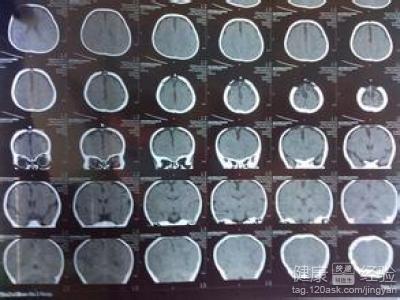

1我們必須知道並不僅僅高熱會引發驚厥,也有一類為無熱驚厥,常發生在一些非感染疾病,如顱內出血、腦水腫、癫痫、腦發育不全、腦積水、小頭畸形,以及營養障礙、代謝紊亂(如低鈣驚厥)、低血糖症、食物中毒、藥物中毒及某些農藥中毒等等。做CT可以幫我們明確病因,便於更好的護理。

3最後我們可以明確知道顱腦CT掃描不會影響孩子的大腦發育。CT掃描所用的X射線,理論上講對人體會有一定的生物效應,可以對身體的細胞產生一定損害。不過對於只做一次CT掃描,所用的輻射劑量是非常低的,完全在安全范圍之內,根本會對孩子的健康產生什麼影響,這個我覺得就不用過於擔心了。